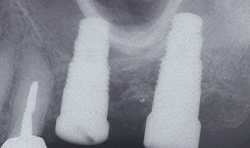

In cases with few residual bones in the posterior maxilla, osteotome with Magnetic Max are useful for transcrestal maxillary sinus floor elevation. Its aim is to create a surgical site for implants by displacing a portion of native residual below bone within the cavity of the maxillary sinus. This particular type of bone is usually found below the sinus floor and, through this technique, is displaced vertically in order to create a new implant alveolar portion.

In the final configuration of the surgically created alveolus, the coronal portion of the crest must give primary implant stability. This will be completed by the coronal bone portion pushed laterally and internally of the sinus cavity, from which a sort of closed “tent” formed by the sinus membrane will keep the cavity closed.

The osteotomy is gradually expanded in 0.5 mm increments using osteotomes inserted to the working depth. The final diameter of the osteotomy is 1.2 mm less than the anticipated implant diameter, depending on local bone density.

Such mechanical sequence of osteotomes progressively condensed internal bone wall of initial hole radially outward with respect to central axis to create high-density bone tissue along a substantial portion of the length of the implant site preparation. The platform of the implants is inserted at the level of the alveolar crest. A minimum insertion torque of 30 Ncm is considered.

Fig. 6c Fig. 6d

Ridge split with Magnetic Max represents a predictable surgical procedure, doesn’t lead to bone injury and doesn’t lead to bone overheating. This surgical technique is rendered safe, less technique sensitive, comfortable and without risk of any form of vertigo (Figs 6a-6e).